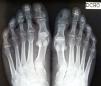

A 44-year-old man visited our department with prominences on both sides of the fifth toe, which had appeared following a walk, on which he had worn tight footwear. The patient complained of discomfort only when pressure was applied to this area. Physical examination revealed external rotation of the fifth toe and increased width of the nail plate on both small toes. Each of these nails was also covered by cuticle, divided by a longitudinal cleft, and the nail plate showed lateral thickening (Fig. 1A and Fig. 2A). Dermatoscopy confirmed that the nail consisted of 2 clearly demarcated parts (Fig. 1, Fig. 2, and Fig. 2B). The patient was not aware of this abnormality in any family member. A simple anteroposterior and lateral x-ray of both feet was requested and ruled out the presence of accessory phalanges or other bone abnormalities (Fig. 3). No treatment was indicated, other than reduction of the direct trauma.

It is rare to find abnormalities in the x-ray of the fifth toe. Of 10 x-rays performed in 1 series, only 3 patients presented a lazy Y on the tip of the distal phalanx, and another patient presented a thorn-like bony excrescence.4 A Y-shaped tip of the terminal phalangeal bone was identified during surgery in 2 patients.4